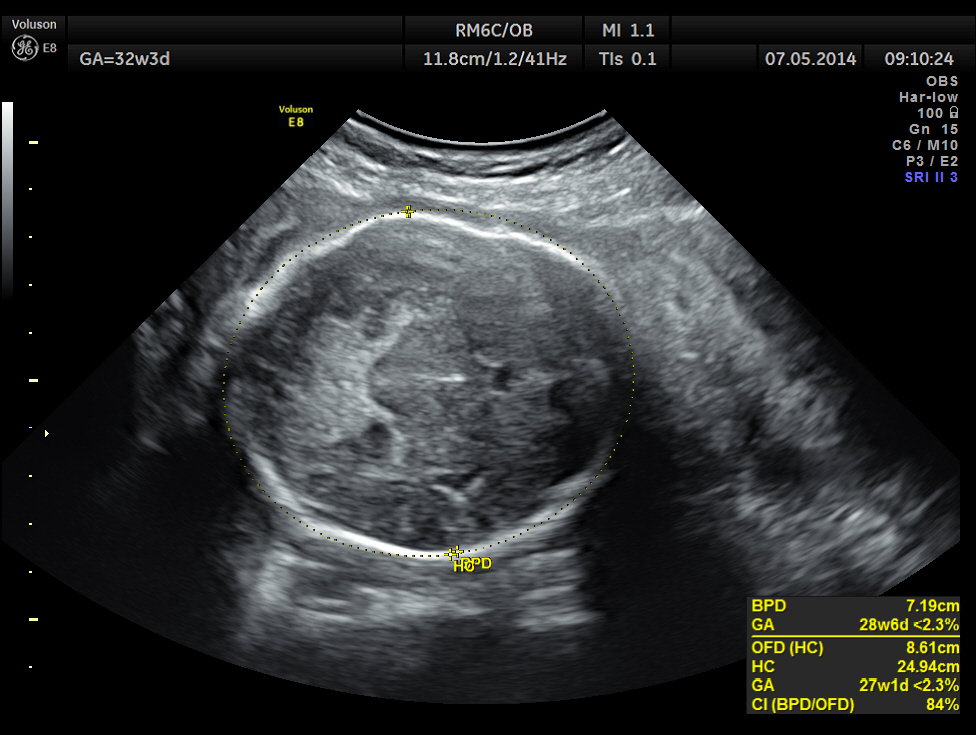

This was a 37 year old lady , a primi gravida referred for evaluation of intra uterine growth restriction. As per LMP the GA was 32 w 3 Days, but as per AUA the GA was 26 weeks . All the long bones were < 5.0 % tile. But cerebellum was 42.7 % tile. There was severe symmetrical growth restriction .